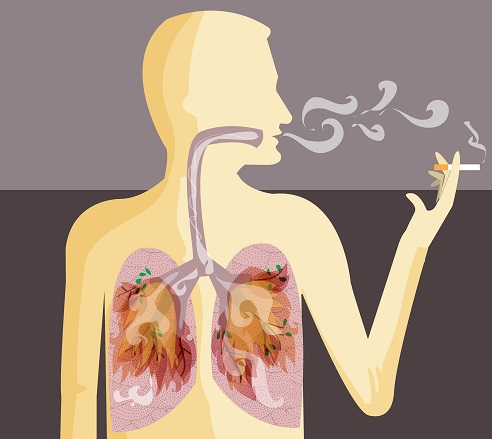

흡연자와 비흡연자를 비교하면 흡연자는 폐암에 걸릴 확률이 낮게는 15배, 높게는 80배까지 높아질 수 있고, 폐암의 마지막 원인 중 하나이기 때문에 흡연자라면 금연을 하는 것이 정말 좋습니다.

또한 흡연의 경우 간접흡연으로 인해 주변 비흡연자에게도 영향을 미칠 수 있으므로 주의해야 합니다. 담배를 피우지 않는다면 야채와 과일을 충분히 섭취하는 것이 좋습니다. 신선할수록 좋으며, 이는 영양소를 섭취하고 시간이 지남에 따라 면역 체계를 구축할 수 있는 좋은 방법입니다.